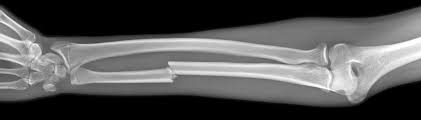

Identify the type of break is present in this xray

closed transverse